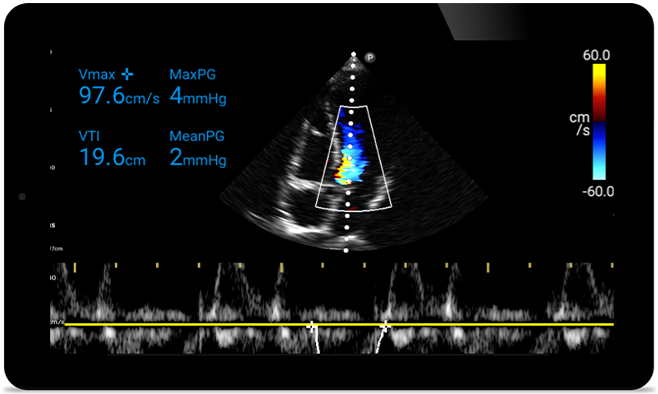

Действуйте быстрее, чтобы защитить сердце пациента

Когда счет идет на секунды, портативный ультразвук может сыграть решающую роль. Lumify может предоставить изображение высокой четкости в любое время и в любом месте.